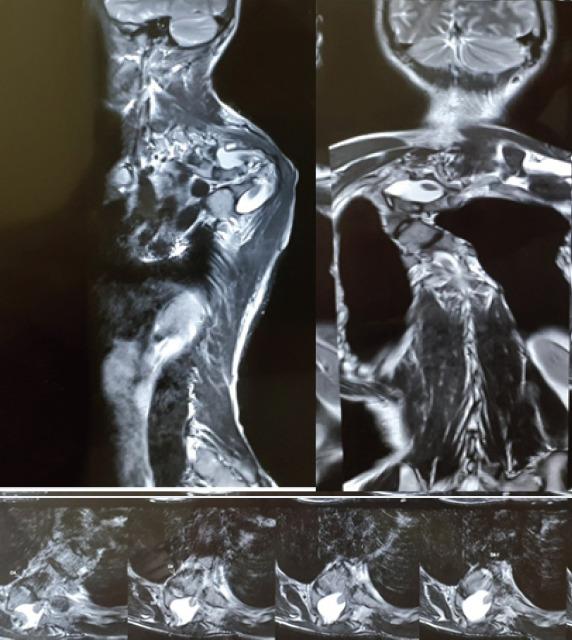

We present a case of 22-year-old male with NF-1 who came to us with gradually progressive upper back deformity and signs of early myelopathy for 2-3 months. The patient had a 100° proximal thoracic kyphosis and 100° scoliosis with no neurological deficit and brisk reflexes. A single stage posterior fixation with three column osteotomy at the apex of the curve was performed.

The kyphosis was corrected to 65° from 100, the scoliosis was corrected to 60° from 100. Clinically, the hump in the upper back was visibly reduced. At 1-year follow-up, the patient remained asymptomatic with no loss of correction and implant breakage on X-ray.

Large dystrophic proximal thoracic kyphoscoliosis is a difficult lesion to treat and can be managed with an all posterior approach, achieving good cosmetic and neurological outcomes, as demonstrated by this case.